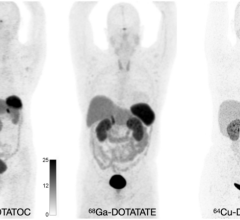

July 18, 2023 — NorthStar Medical Radioisotopes, LLC, a global innovator in the development, production and ...